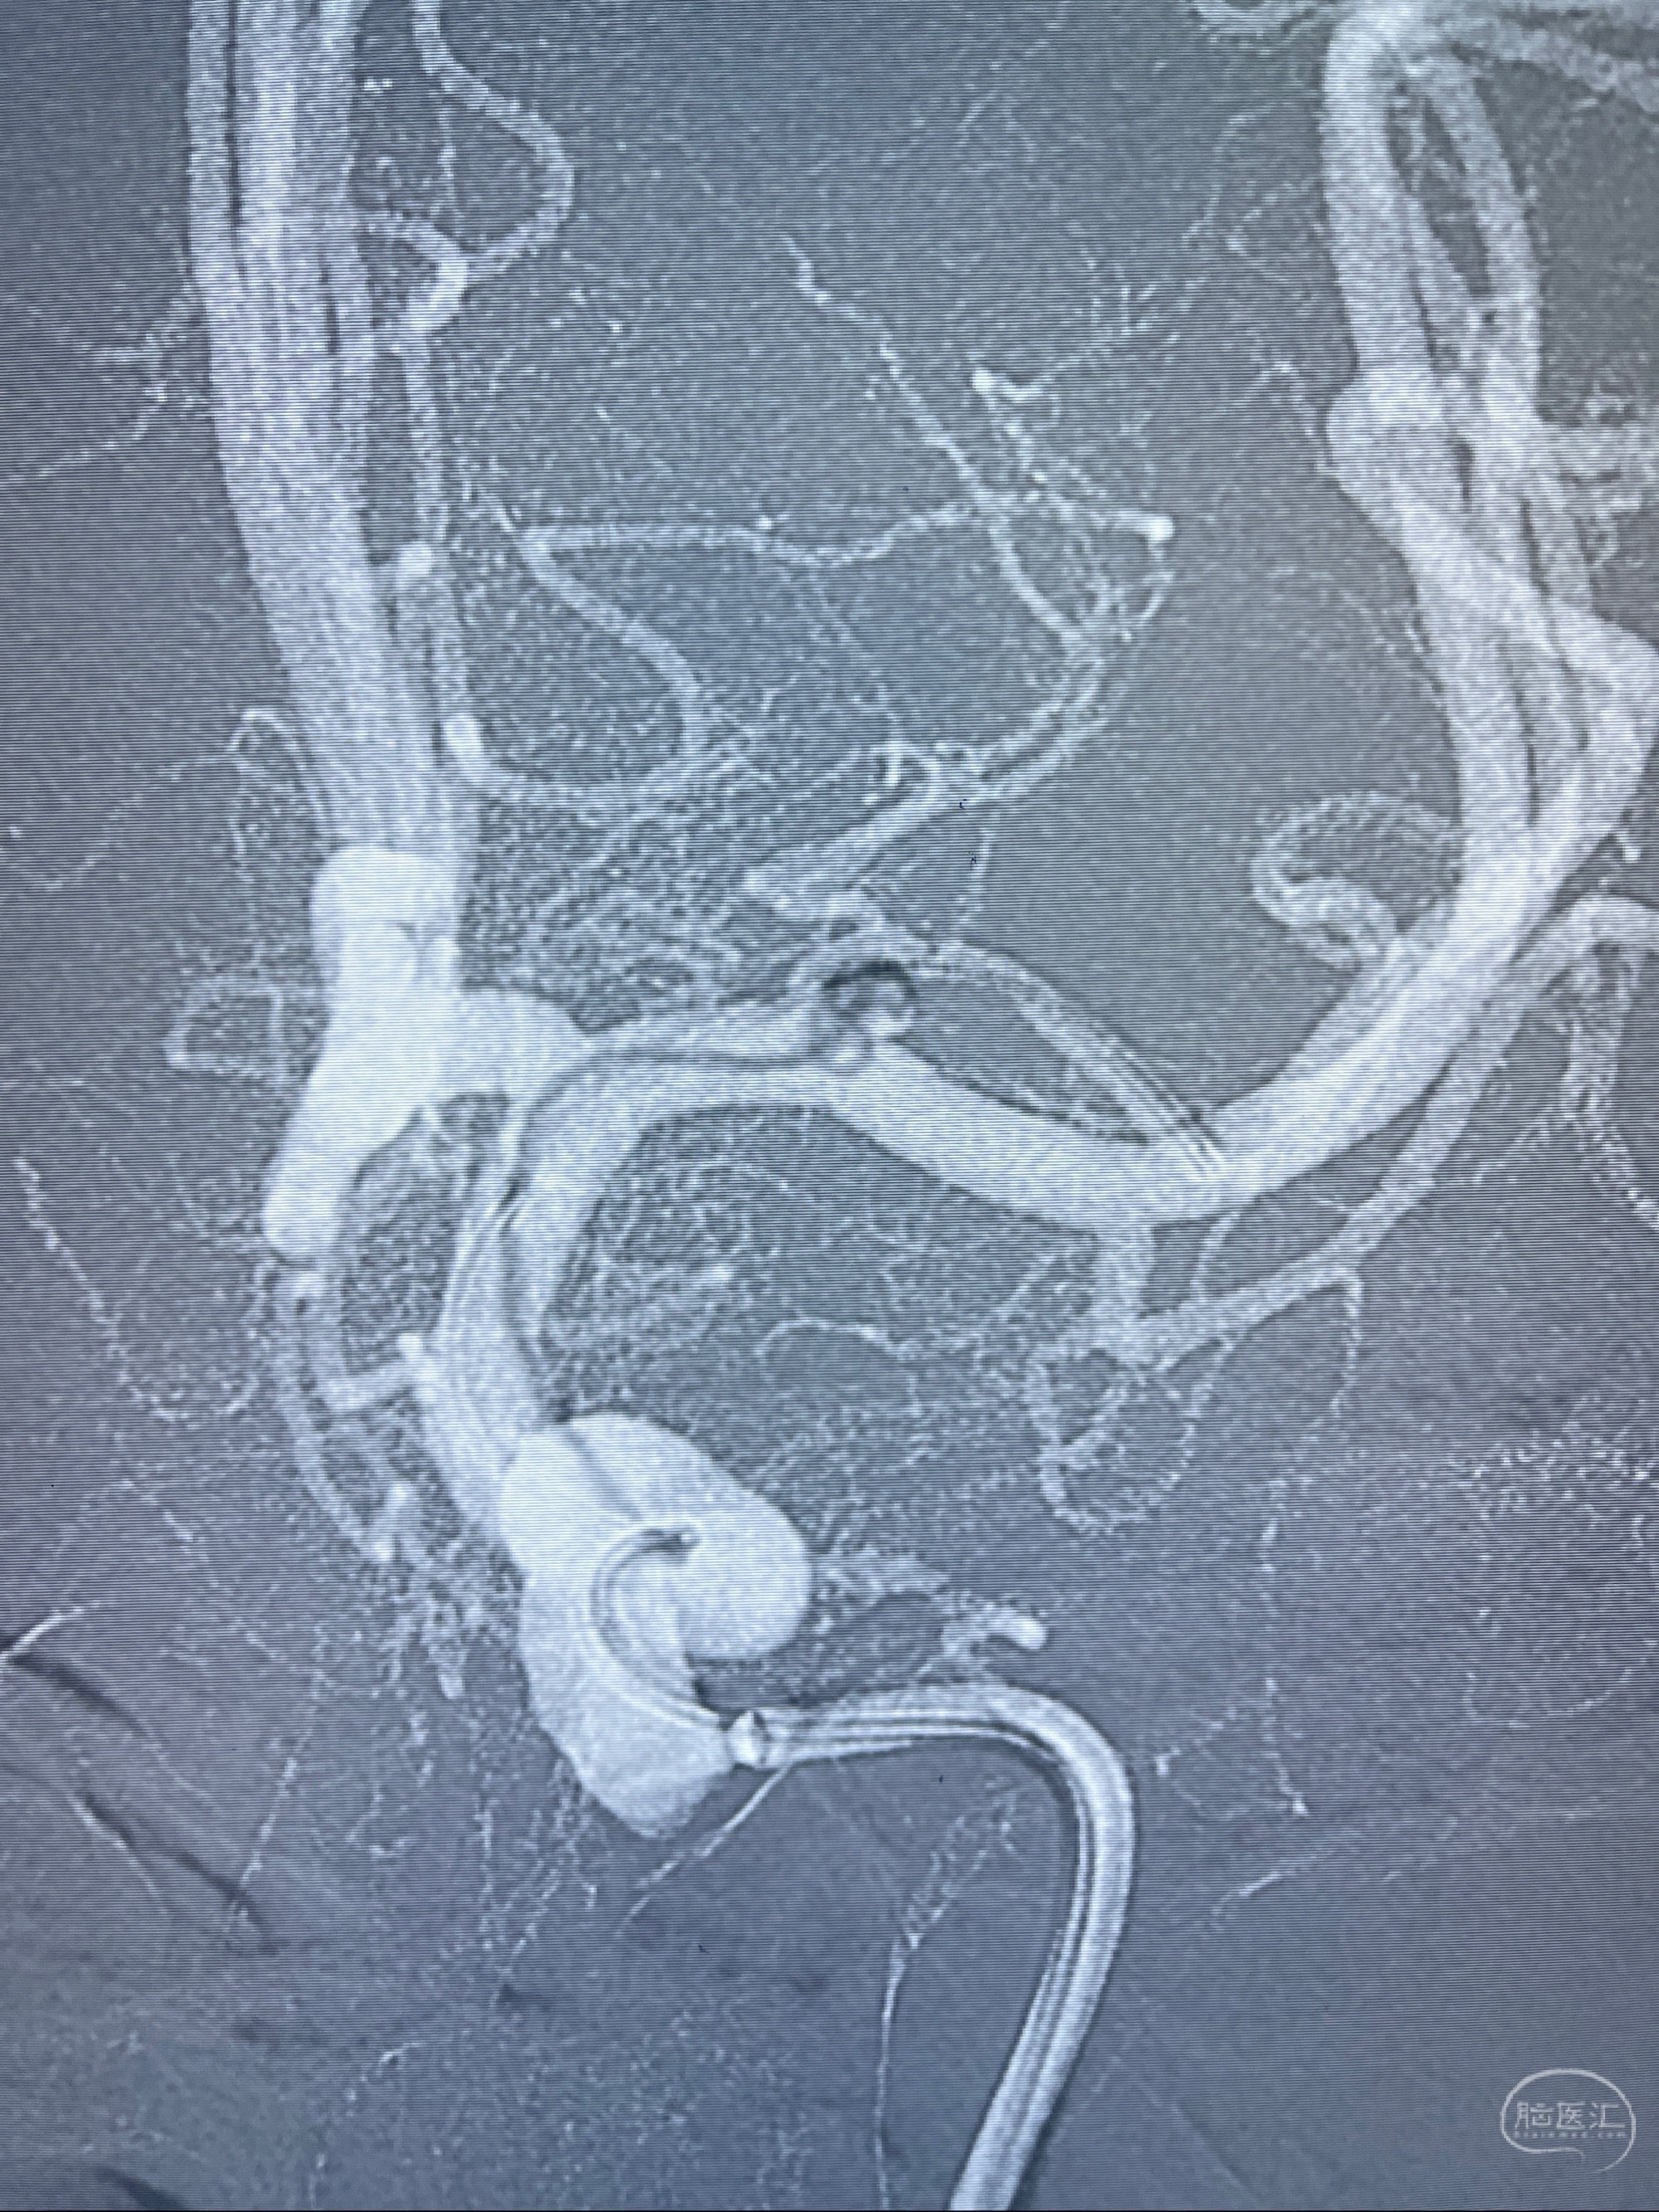

2023-08-14DSA:

左侧大脑中动脉动脉瘤,约2.6-2.8-3.4-2mm大小(瘤颈部、瘤体部、瘤高)

1.左侧大脑中动脉动脉瘤,约2.6-2.8-3.4-2mm大小(瘤颈部、瘤体部、瘤高)